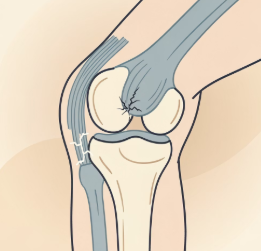

무릎 안쪽을 지지하는 내측 인대가 늘어나거나 손상되면 통증이 발생합니다.

넘어지거나 외부 충격으로 무릎이 안쪽으로 꺾일 때 흔히 나타납니다.

눌렀을 때 통증이 느껴지고, 붓거나 열감이 동반되기도 합니다.